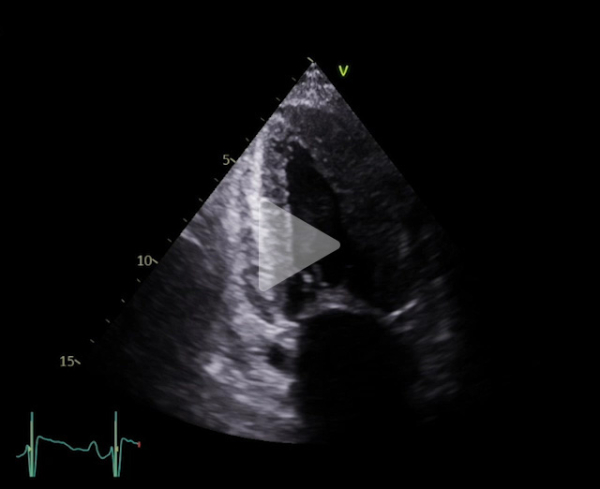

Vidéo 1

FEVG 40% en Simpson biplan, 45-50% visuellement. GLS -7%. Hypokinésie des bases et hyperkinésie de l'apex. VG non dilaté (DTDVG = 35mm, VTDVG =54ml/m2), hypertrophié (SIV = 18.5mm, PPVG = 19mm).

- DC = 3l/min, IC = 1.6l/min/m2 avec CCVG = 21mm et ITV sous Ao = 8cm

- OG dilatée à 40mL/m² (21cm2). OD dilatée à 19cm2

- Valve aortique tricommissurale, fine, pas de sténose ou fuite. Valve mitrale épaissie, pas sténose ou fuite

- Profil mitral restrictif, pressions de remplissage VG élevées (E/A =2.6, E/e’ moy = 22)

- Cavités droites non dilatées (Anneau tric =35mm)

- Fonction VD altérée (TAPSE = 7.7mm, S tric = 5.9cm/s)

- PAPS estimée sur IT modérée à 30 + 15mmHg (TAP 82ms)

- VCI dilatée ( 22mm), non compliante

- Lame péricardique minime